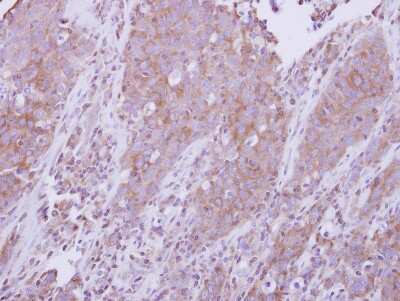

Immunohistochemistry-Paraffin: MyD88 Antibody [NBP2-19448]

Immunohistochemistry-Paraffin: MyD88 Antibody [NBP2-19448] - Human lung papillory cancer, using MYD88 antibody at 1:500 dilution. Antigen Retrieval: Trilogy™ (EDTA based, pH 8.0) buffer, 15min.